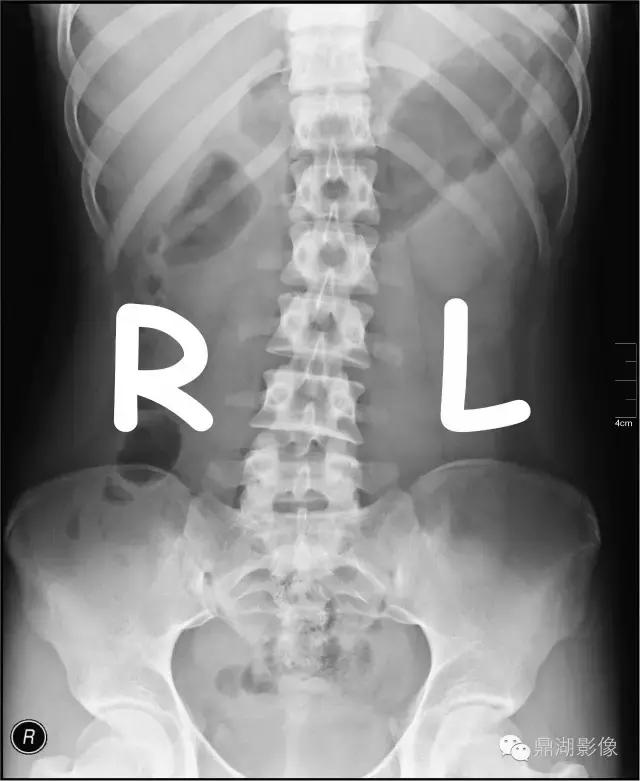

由上图标注可以看出腹部平片左边的图像是被检者的右侧,右边的图像是被检者的左侧。这个是基础知识。